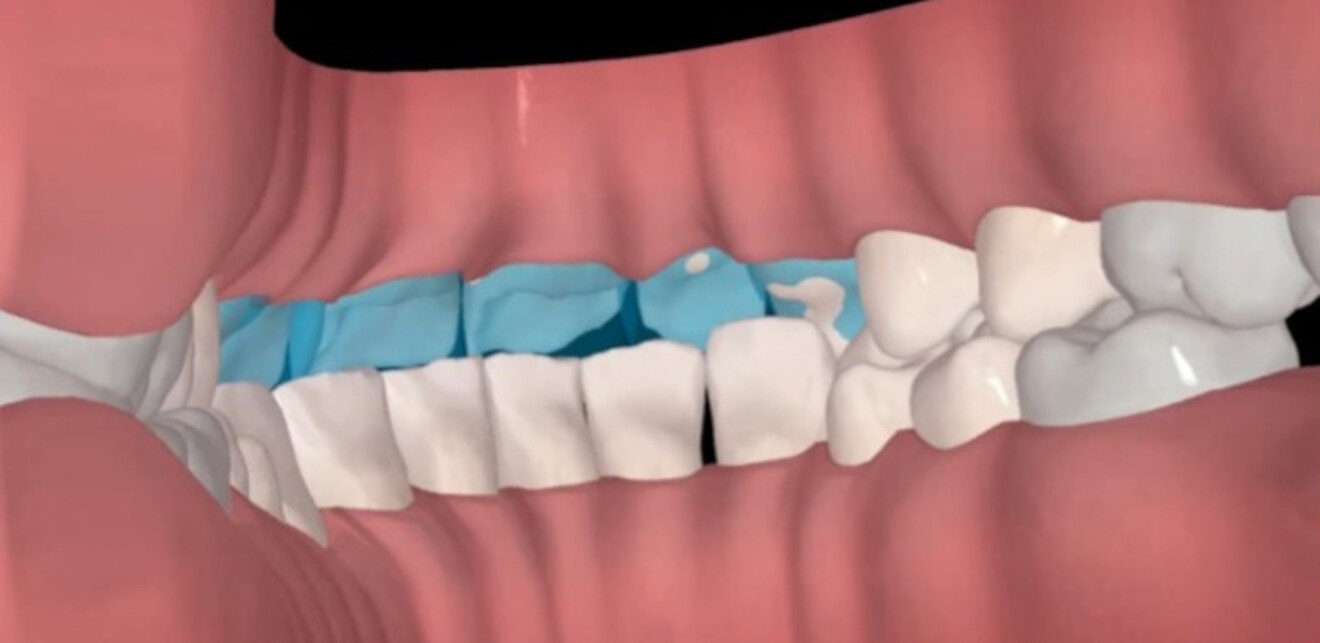

Figs. 1a & b: Side-by-side cross-sectional analysis of the initial (a) and post-restorative treatment position (b), highlighting vertical space creation with orthodontic treatment.

An approach involving only restorative dentistry was considered; however, owing to the heavy incisal intercuspation as a result of acid erosion, wear and overeruption, either significant further reduction of the maxillary and mandibular tooth structure or increase of the vertical dimension of occlusion through full mouth-rehabilitation would have been required. An alternative option of a short course (14 weeks) of Invisalign treatment was discussed as a means of maximising vertical, interproximal and inter-arch space while maintaining the stable, functional posterior occlusion and vertical dimension of occlusion.

The importance of aligner compliance was stressed, and the patient progressed well with treatment, which included take-home whitening along with the aligner therapy. Analysis of the situation after aligner therapy was performed, including review with exocad software (Figs. 2–5). This was followed by the placement of anterior resin composite restorations (IPS Empress Direct, Bleach-L Dentin; Ivoclar). No preparation or reduction of the remaining dentition was performed—instead, space was created via preparation with plastic.